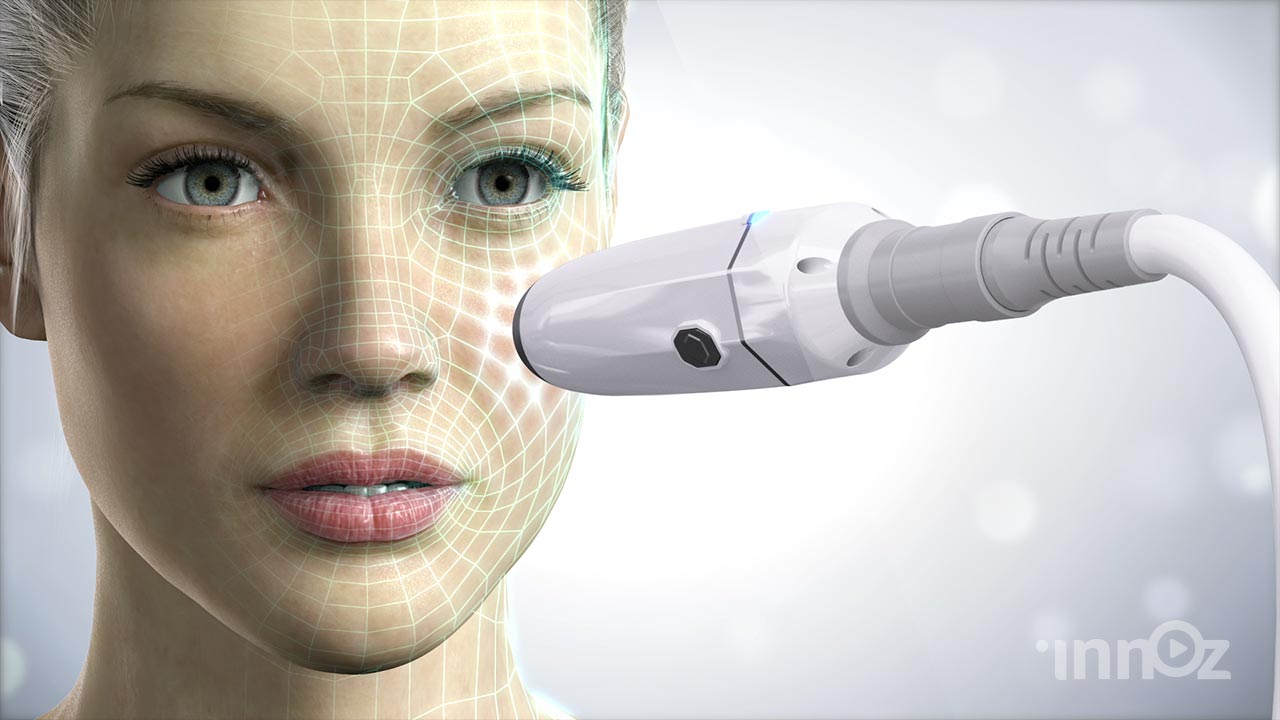

의료, 건설, 산업, VR AR, AI 등 고퀄리티 3D영상제작

이노즈는 AI영상제작, 3D영상 제작 전문기업으로, 다양한 산업 분야에 걸쳐 혁신적이고 몰입감 있는 3D 콘텐츠를 제공합니다. 제품 홍보, 건설 시뮬레이션, 애니메이션 등 맞춤형 영상으로 고객사의 가치를 시각적으로 효과적으로 전달합니다. 고품질의 3D 시각화와 창의적인 연출을 바탕으로, 고객의 목표를 실현하는 독창적이고 강력한 시각적 경험을 제공합니다. 이노즈의 포트폴리오는 고객의 아이디어를 현실로 구현한 다양한 성공적인 프로젝트로 가득합니다.

2023 쉬엔비 다이아코어등 고주파 치료기 전제품

2023 제이시스메디칼 고주파치료기 덴서티 영상제작

2022 텐텍 텐써마 고주파 의료장비 영상제작

2022 시지바이오 페이스템 필러 의료 영상제작